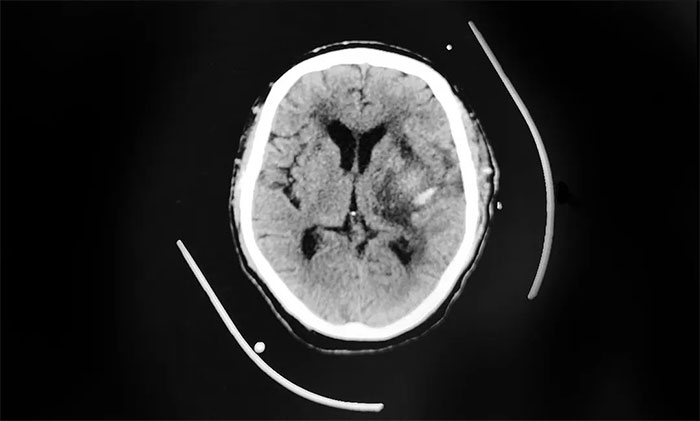

查頭部CT提示腦出血,急行“血腫清除術”,術后轉重癥監(jiān)護室。由于老王手術后意識持續(xù)昏迷,只能經口氣管插管,接呼吸機輔助呼吸。之后,還迫于無奈進行了氣管切開術。

▲ 左側基底節(jié)區(qū)出血